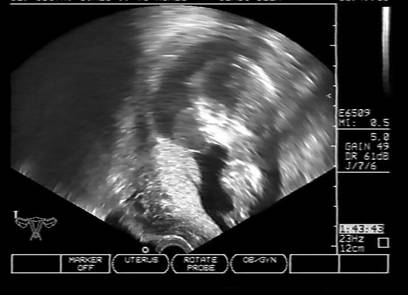

Fig. nr. 249. Hidrocefalie interna unilaterala aparuta la 28 sapt si cu evolutie rapida, postpartum se confirma suspiciunea de diagnostic: hemoragie cerebrala